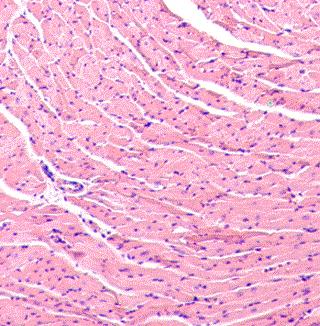

A review article has been published in the journal Current Pharmaceutical Design which provides an overview of therecent literature discussing the different clinical forms of heart disease resulting from virus infections including the prognosis, and current therapies. Many common viruses causing respiratory illness, including enteroviruses and influenza viruses among others, have the potential to infect the heart and initiate an immune response to the infection. These viruses can also produce mild to lethal cardiac injury.

Viral myocarditis is a leading cause of sudden unexpected death from cardiovascular causes primarily in men who are less than 40 years in age. Women either have a lower incidence of viral myocarditis or develop less severe infection than men. The infection can exist as an acute and self-limiting form (fulminant myocarditis) in which patients usually recover once the virus is cleared. However, patients with severely compromised cardiac function may require temporary use of a left ventricular assist device. Other patients develop chronic myocarditis, a progressive inflammation of the heart muscle, which results either from the establishment of persistent virus infections that the body cannot eliminate or the induction of autoimmunity to heart proteins. Chronic myocarditis lasting many months and years ultimately results in dilated cardiomyopathy which may require heart transplantation. It is estimated that up to 30% of allclinical dilated cardiomyopathy cases result from underlying viral infections.